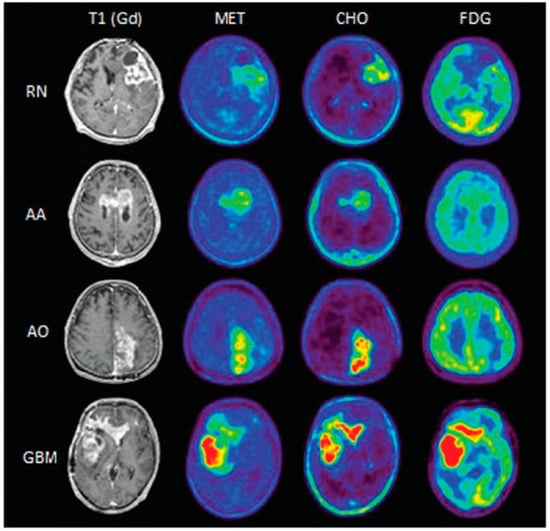

- Takenaka, S.; Asano, Y.; Shinoda, J.; Nomura, Y.; Yonezawa, S.; Miwa, K.; Yano, H.; Iwama, T. Comparison of 11c-methionine, 11c-choline, and 18f-fluorodeoxyglucose-positron emission tomography for distinguishing glioma recurrence from radiation necrosis. Neurol. Med. Chir. 2014, 54, 280–289. [Google Scholar] [CrossRef]